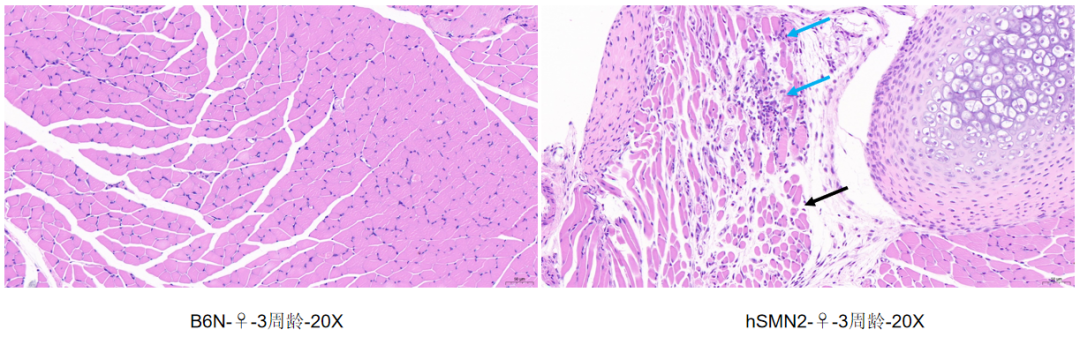

肌肉组织HE染色

相对于B6N野生型小鼠,hSMN2小鼠肌肉组织可见少量肌细胞坏死,胞质崩解,伴有极少量的淋巴细胞浸润(蓝色箭头),周围可见肌细胞萎缩,体积减小,肌细胞间隔增宽,排列疏松(黑色箭头)。